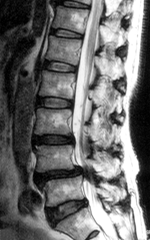

MRIによって神経の圧迫の程度がわかります。

第4腰椎が前方(図の左側)へ移動している

4と第5腰椎の間で硬膜管が圧迫されている